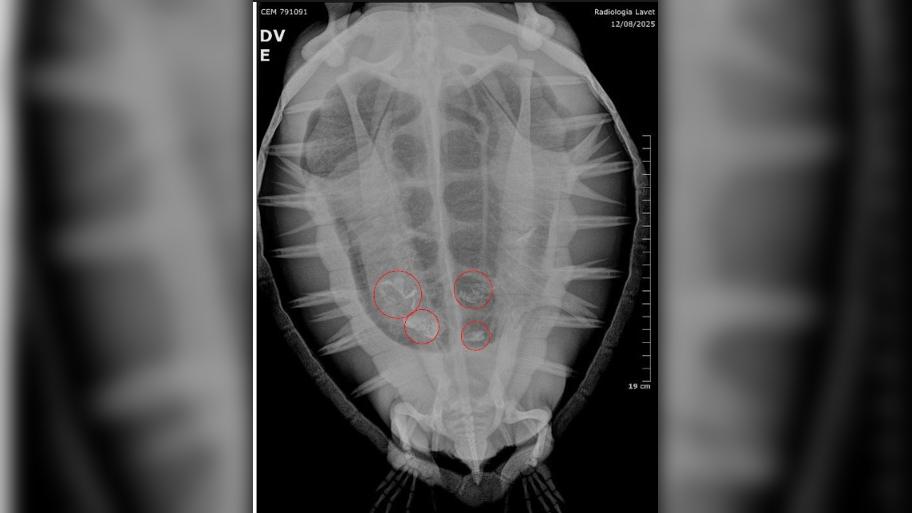

O Laboratório de Ecologia e Conservação da Universidade Federal do Paraná (LEC-UFPR), por meio do Projeto de Monitoramento de Praias da Bacia de Santos (PMP-BS), vem registrando nos últimos meses encalhes de tartarugas-verdes e pinguins-de-Magalhães debilitados, muitos com fragmentos plásticos no organismo.

Os animais são encaminhados ao Centro de Reabilitação, Despetrolização e Análise de Saúde de Fauna Marinha (CReD-UFPR), em Pontal do Paraná, onde recebem atendimento especializado. Os dados se somam a uma década de monitoramento e reforçam a gravidade da poluição plástica nos oceanos.

Durante o inverno, período em que aumenta o número de encalhes de animais migratórios, a equipe do PMP-BS registrou casos de tartarugas com ingestão de resíduos.

“Infelizmente, acabamos atendendo vários animais marinhos com plástico, tanto fragmentos rígidos quanto embalagens maleáveis. Já tivemos casos em que o animal chegou vivo ao CReD, mas não resistiu”, afirmou a médica veterinária Carolina Jorge.